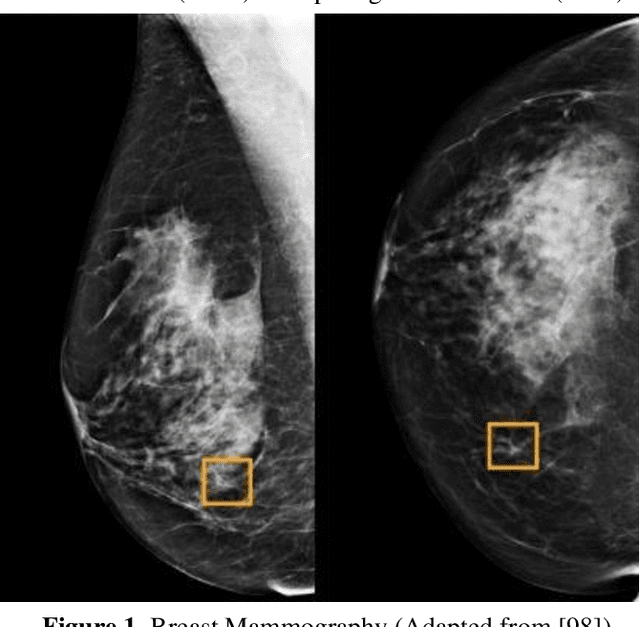

Abstract:Breast cancer is a common fatal disease for women. Early diagnosis and detection is necessary in order to improve the prognosis of breast cancer affected people. For predicting breast cancer, several automated systems are already developed using different medical imaging modalities. This paper provides a systematic review of the literature on artificial neural network (ANN) based models for the diagnosis of breast cancer via mammography. The advantages and limitations of different ANN models including spiking neural network (SNN), deep belief network (DBN), convolutional neural network (CNN), multilayer neural network (MLNN), stacked autoencoders (SAE), and stacked de-noising autoencoders (SDAE) are described in this review. The review also shows that the studies related to breast cancer detection applied different deep learning models to a number of publicly available datasets. For comparing the performance of the models, different metrics such as accuracy, precision, recall, etc. were used in the existing studies. It is found that the best performance was achieved by residual neural network (ResNet)-50 and ResNet-101 models of CNN algorithm.